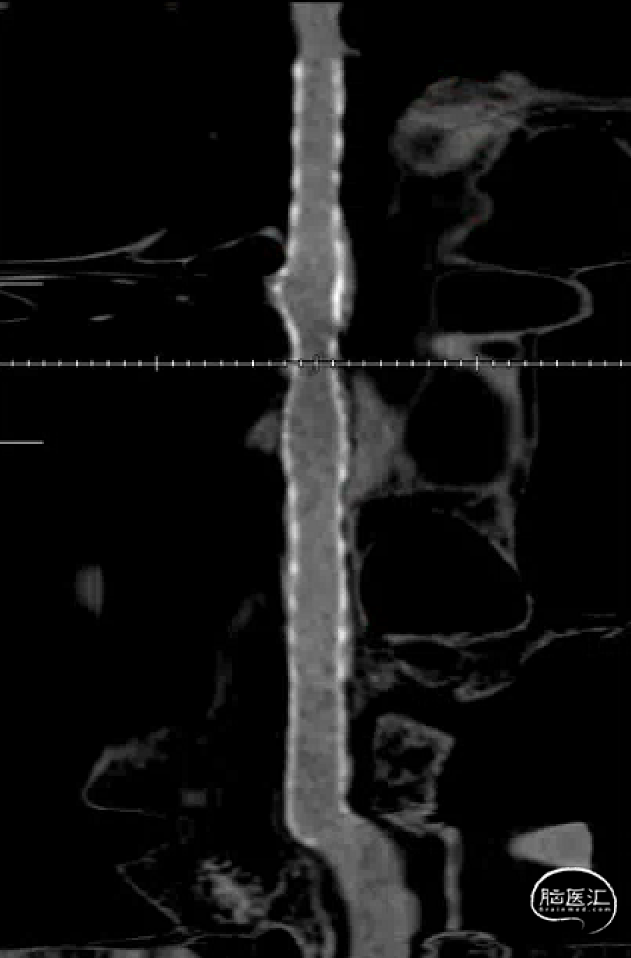

左侧颈内动脉重建(左侧狭窄及扩张较右侧更甚)

Cat5提供稳定通路,引入3.5mm×10mmHiryu球囊扩张由远端及近端扩张狭窄段及支架贴壁欠佳处

扩张后再次复查造影示支架打开及贴壁较前明显改善

稀释造影提示支架贴壁可,狭窄改善